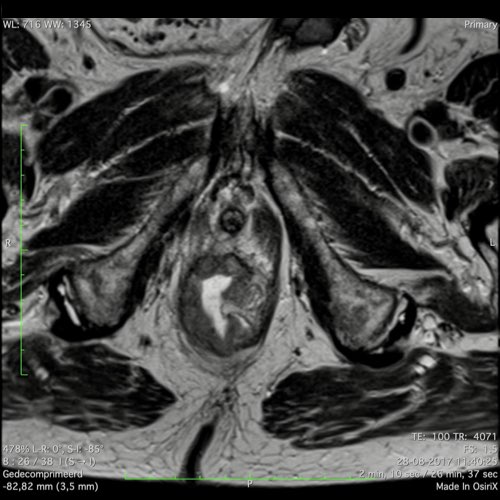

Hình ảnh

Các hình ảnh được cung cấp cho thấy ung thư biểu mô tế bào nhẫn với tình trạng dày lan tỏa thành trực tràng, hình ảnh bia bắn điển hình, và sự xâm lấn mỡ mạc treo trực tràng.